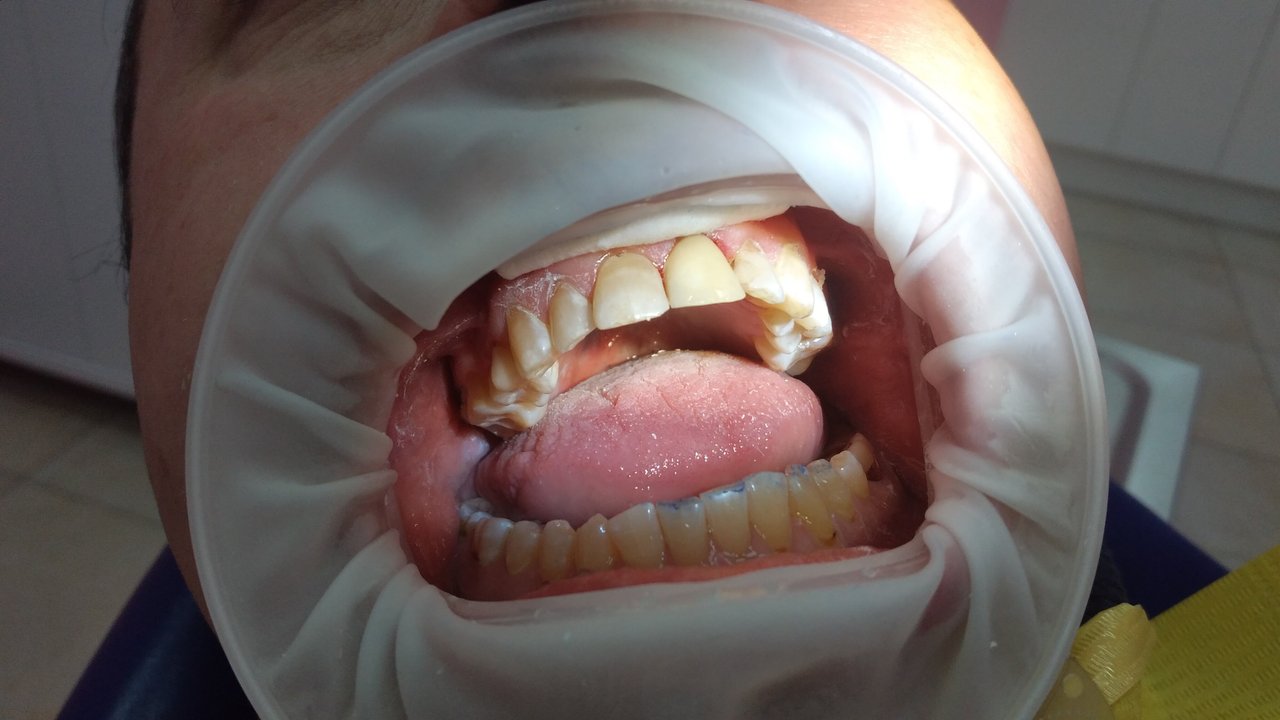

В центре осуществляется лечение пульпита и кариеса, базовое лечение зубов.